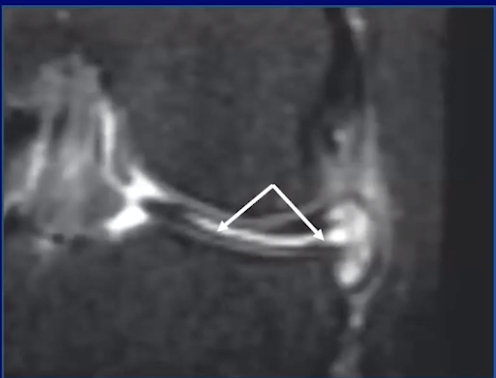

Hoop stress

• We need to think of the meniscus as a tub of toothpaste with a person squeezing the center of the toothpaste container

• When we do this the toothpaste with clump up and push out on either side of the force pushing on the center

• If the toothpaste container has the lid on then no toothpaste will spill out

• This is the same thing as the meniscus

• With the meniscus we have a piece of tissue that has a force being applied to the center of it resulting in clumping on the edges

• The central force is the femoral condyle

• The clumps of toothpaste within the jar are the meniscal triangles

• The meniscus does not get forced out of the knee joint because we have ligaments keeping it in place (the toothpaste does not get spilled out because the cap is on)

• The root ligaments keep it in place medially

• The menisco-femoral ligament and coronary ligament keep it in place laterally

• If these ligaments are torn then the meniscus can float around and be unstable (the toothpaste lid is off and the toothpaste has fallen out of the container)